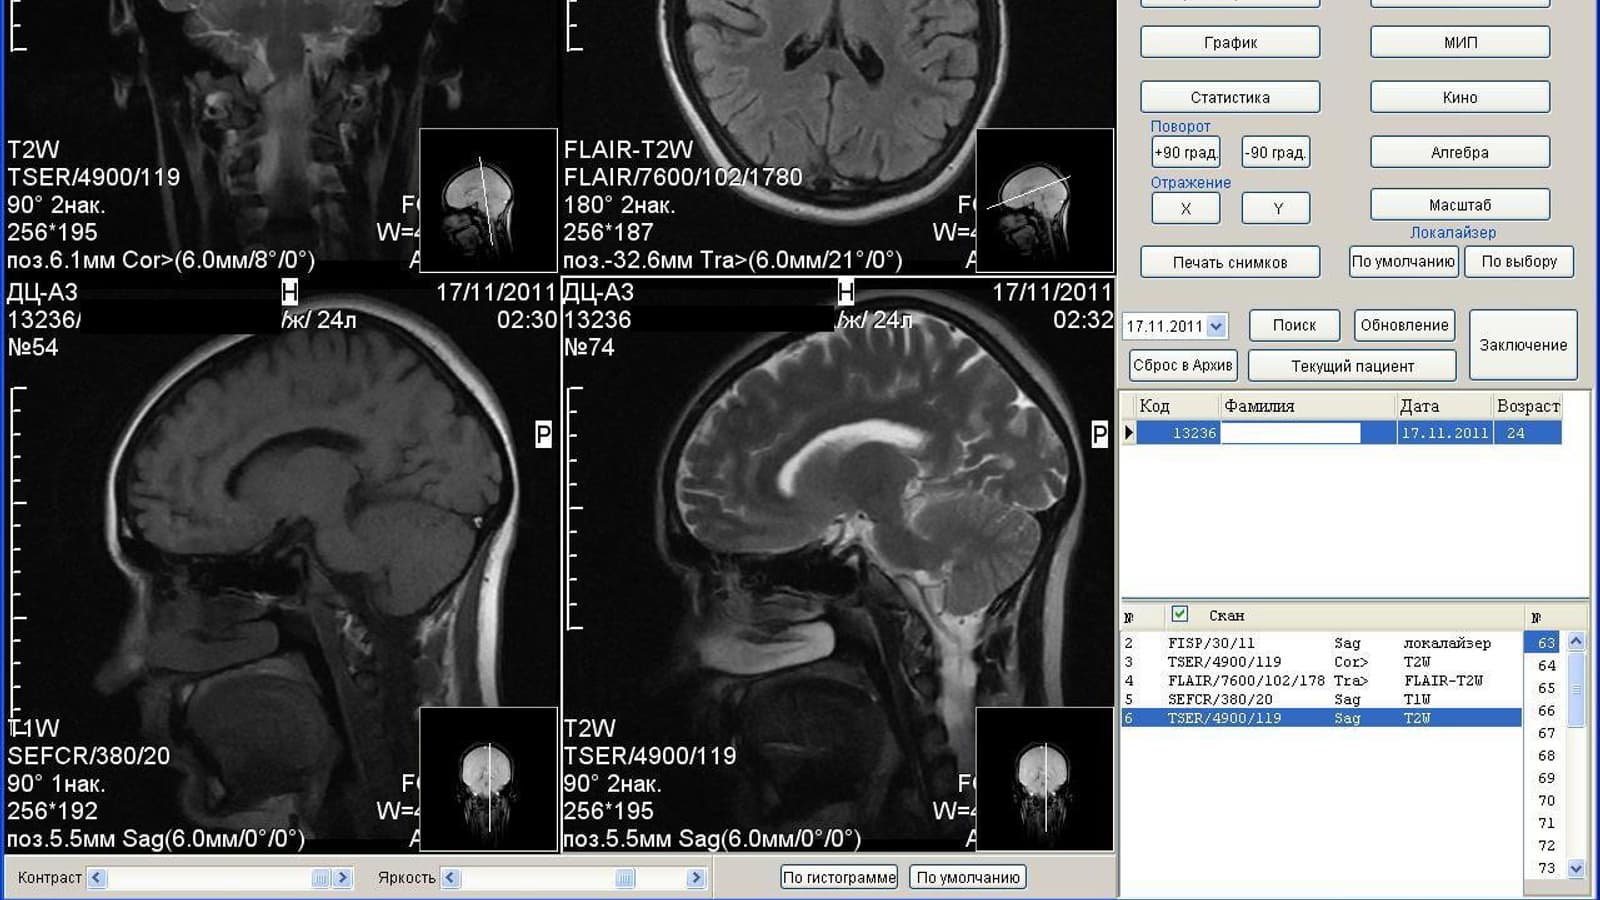

Результаты аппарата МРТ Аз-300

Отмечается, что ученые восстановили функциональные сети головного мозга здоровых людей и пациентов с депрессией. Методика, получившая название «консенсусный подход», выявила различия в результатах функциональной МРТ у двух групп людей.